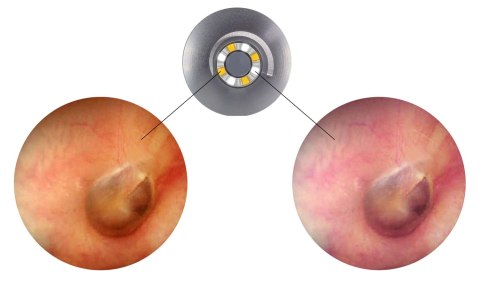

Dwa kolory oświetlenia 2×4 diody LED - 3000K i 6000K. Przełączanie dzięki jednemu przyciskowi. Po 3 minutach otoskop Luxamed Auris LED zoastaje automatyczne wyłączony (oszczędność energii). Żywotność diod LED stanowi około 100 000 godzin.

Światło białe ciepłe jest podobne do standardowych żarówek żarnikowych, co stanowi optymalne oświetlenie w trakcie badanie otoskopowego.

Generowane światło przez otoskop Luxamed jest poprzez diody ulokowane na części zewnętrznej główki optycznej, przy miejscu założenia wziernika. Powoduje to, że transmisja światła nie jest zachwiana i płynie we właściwe miejsce. Nie dochodzi do braku ograniczenia pola widzenia.